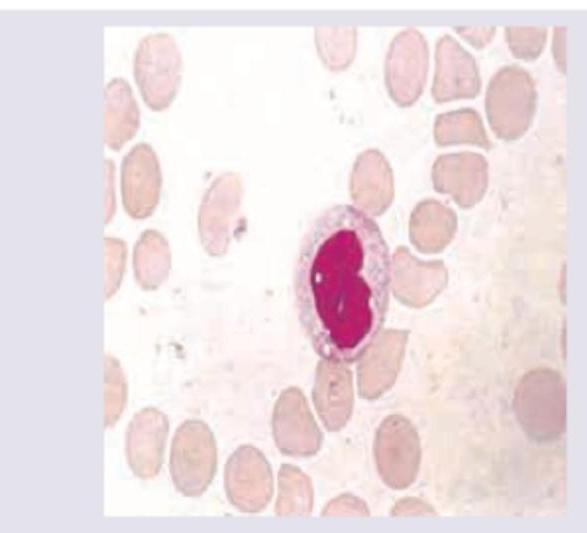

The following cell type is seen in peripheral smear of a patient with membrane over the tonsils. All can be used in treatment except?

A 12-year-old child presents with fever, sore throat for 3 days and posterior cervical lymphadenopathy. Peripheral smear was performed. Diagnosis is?

Explanation: ***Acyclovir*** - The image depicts an **atypical lymphocyte** (Downey cell), characteristic of **infectious mononucleosis**, commonly caused by the **Epstein-Barr virus (EBV)**. - Acyclovir is an **antiviral medication** primarily used for **herpes simplex virus (HSV)** and **varicella-zoster virus (VZV)** infections, and it is **not effective against EBV**. *Prednisolone* - **Corticosteroids** like prednisolone may be used in severe cases of infectious mononucleosis, especially when complications such as **airway obstruction** due to tonsillar hypertrophy, **hemolytic anemia**, or **thrombocytopenia** are present. - They help to **reduce inflammation** and suppress the immune response. *IVIG* - **Intravenous immunoglobulin (IVIG)** can be used in rare, severe, or complicated cases of infectious mononucleosis, particularly if there are significant **hematologic complications** (e.g., severe thrombocytopenia, severe hemolytic anemia) or in patients with **immunodeficiency**. - IVIG provides **passive immunity** and modulates the immune response. *Acetaminophen* - **Acetaminophen (paracetamol)** is a common **analgesic** and **antipyretic** used to manage symptomatic relief for fever, sore throat, and muscle aches associated with infectious mononucleosis. - It helps to **alleviate discomfort** and improve patient well-being during the acute phase of the illness.

Explanation: ***Infectious mononucleosis*** - The image shows an **atypical lymphocyte** (Downey cell), characterized by a large, irregularly shaped nucleus and abundant, basophilic cytoplasm, often indenting surrounding red blood cells. These are characteristic of infectious mononucleosis. - The clinical presentation of **fever**, **sore throat**, and **posterior cervical lymphadenopathy** in a 12-year-old child is typical for infectious mononucleosis, commonly caused by the **Epstein-Barr virus (EBV)**. *Hodgkin lymphoma* - While Hodgkin lymphoma presents with lymphadenopathy, it typically involves **Reed-Sternberg cells** on biopsy, which are not seen in a peripheral smear. - Furthermore, the clinical course and presentation of Hodgkin lymphoma are usually more chronic and would not typically present with the acute viral-like syndrome described. *CLL* - **Chronic Lymphocytic Leukemia (CLL)** is a malignancy of mature B lymphocytes, primarily affecting older adults, and would be rare in a 12-year-old. - Peripheral smears in CLL show mature-appearing lymphocytes, often with "smudge cells," which are distinct from the atypical lymphocytes seen in the image. *Herpangina* - Herpangina is a viral illness causing **fever** and **painful mouth sores** (vesicles and ulcers) in the posterior oropharynx, often caused by Coxsackievirus. - While it can cause fever and sore throat, it does not typically present with significant lymphadenopathy, especially **posterior cervical lymphadenopathy**, and would not show atypical lymphocytes on a peripheral smear.